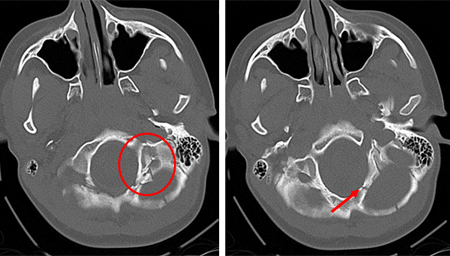

[Figure caption and citation for the preceding image starts]: Occipital fracture extending to foramen magnum: risk of brainstem compression by haematoma.From the teaching collection of Demetrios Demetriades, Division of Trauma and Surgical Intensive Care, LAC/USC Trauma Center, Keck School of Medicine at USC; used with permission [Citation ends].

[Figure caption and citation for the preceding image starts]: Linear parietal fracture without depressionFrom the teaching collection of Demetrios Demetriades, Division of Trauma and Surgical Intensive Care, LAC/USC Trauma Center, Keck School of Medicine at USC; used with permission [Citation ends].

[Figure caption and citation for the preceding image starts]: Fracture of temporal bone.From the teaching collection of Demetrios Demetriades, Division of Trauma and Surgical Intensive Care, LAC/USC Trauma Center, Keck School of Medicine at USC; used with permission [Citation ends].